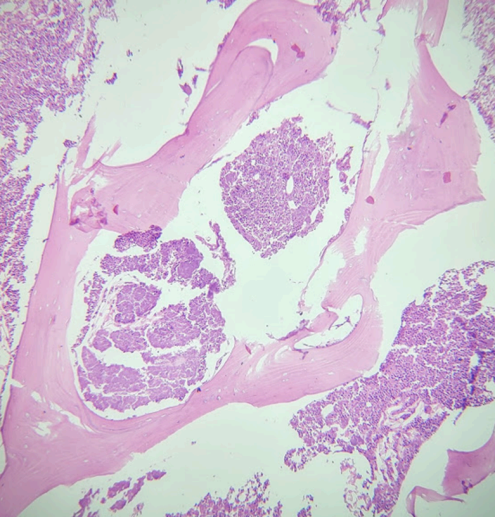

El estudio histológico evidenció osteomielitis crónica supurativa asociada a necrosis ósea. (Fig. 1 a 3)

Figura 2: Osteonecrosis e infiltrado inflamatorio agudo